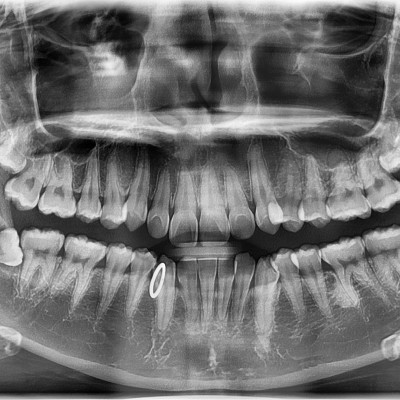

• 163

#38 사랑니 발치 N새글 #38 사랑니 발치 구강 외과 전문의가 당일 발치했습니다. -----------------------------..

작성자 이턱이 작성일 17:31 조회 1